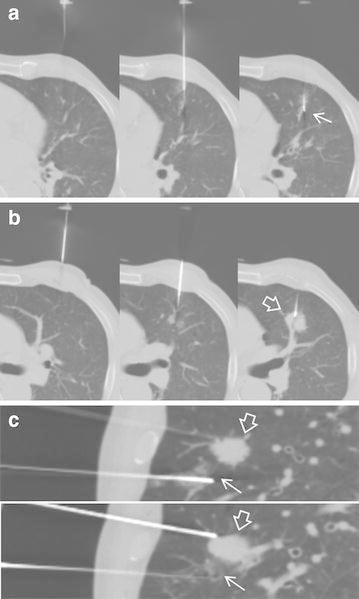

The purpose of our study was to evaluate the feasibility and safety of CT-guided percutaneous lung biopsy using two needles in difficult and poorly cooperative patients; and to examine the usefulness of the malpositioned first needle in tissue sampling with a second needle. This study included 17 consecutive patients with unsuccessful first insertion of the biopsy needle in the normal lung parenchyma and re-attempted tissue sampling through another puncture site using a second needle with the first needle retained in position until completion of the biopsy. We examined the difficult factors in biopsy that led to a failed first attempt, success rate of tissue sampling, procedure-related complications, and usefulness of the malpositioned needle. There were 1 or multiple difficult factors in all patients. In all 17 patients, core samples were successfully obtained using a second needle. Post-procedure pneumothorax and parenchymal hemorrhage occurred in 4 and 3 patients, respectively. The first needle was used as a navigational reference point for lesion localization in all patients and as an anchor restricting the mobility of the lung in patients with pneumothorax or poor breath holding capacity. CT-guided needle biopsy of the lung using a second needle without removing the first malpositioned needle is feasible and safe. During biopsy procedures in difficult or poorly cooperative patients, the malpositioned needle provides a navigational reference point or serves as an anchor to hold the movable lung.